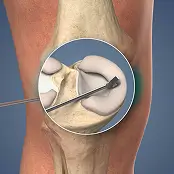

Knee Orthopedic Surgery